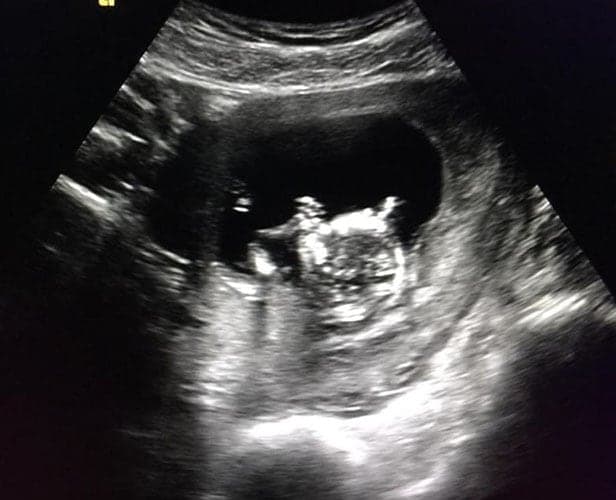

Ultraschallbilder aus dem 2. Trimester (13. bis 28. SSW)

Im 2. Trimester bekommt man oft die schönsten „Ganz-Körper“ Ultraschallbilder. Das Baby ist nun so groß, dass man alles gut erkennen kann und noch nicht zu groß, so dass es noch ganz auf das Bild passt. In dieser Zeit lässt sich meist das Geschlecht bestimmen, wobei manche Babys es einfach nicht preis geben wollen und sich immer so drehen, dass man nichts erkennen kann.